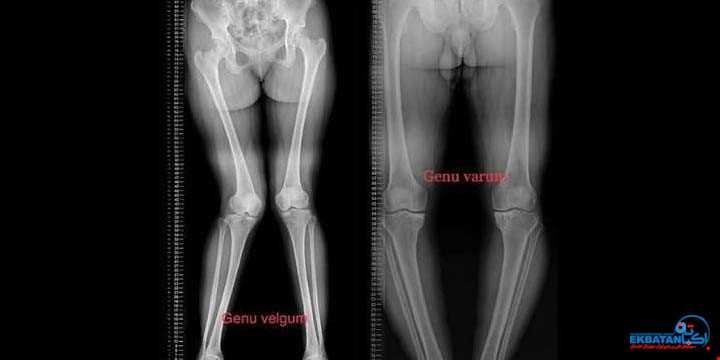

درمان پا پرانتزی و پا ضربدری در کودکان

رادیولوژی اکباتان - مرکز تخصصی بررسی الاینمنت اندام تحتانی با دیتکتور Long iRay و اندازه گیرهای دیجیتال دقیقمقدمهالاینمنت (Alignment) یا راستای اندام ...

نقش رادیوگرافی الاینمنت (Three Joint View) در پا پرانتزی و پا ضربدری کودکان

پا پرانتزی و پا ضربدری؛ از مشکلات رایج دوران رشد کودکان می باشد.پا پرانتزی (Genu Varum) و پا ضربدری (Genu Valgum) از شایع ترین ناهنجاری های محور اندام ...